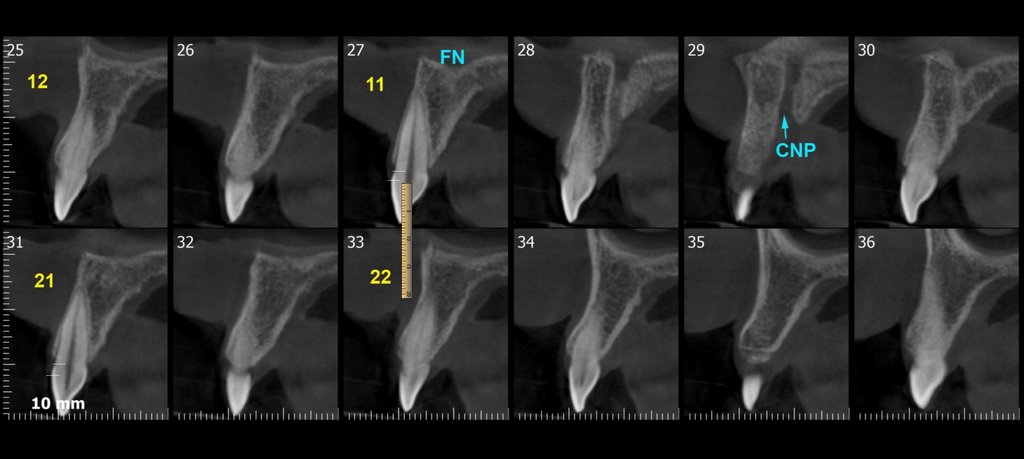

Crown lengthening 11 - 8mm

10,5mm

9,5mm

8,7mm

10,2mm

8,3mm

0,5mm

1mm